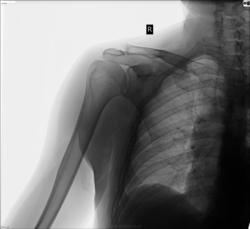

Мужчина, 47 лет. Жалобы на боль при отведении руки назад. "Сустав болит" - говорит. Прочих жалоб пока нет. Кто-то считает, что плечевой сустав в чём-то особый, что артроз в нём редко возникает, чуть ли никогда. Всё чаще импиджментом все изменения и болезненности описываем. Здесь его тоже напишем или признаки артроза всё же узрим?)

С плечевым суставом, на мой взгляд, все в порядке

Акромиальный конец ключицы "погрызенный", узурированный. как-то больше - на артрит...

Акромеальный конец ключицы "порушен".Мысль об онкологии.

А по-моему, он просто сломан. Бывают там усталостные переломы?

Подумала примерно то же, что и maker4ik :травма в анамнезе и старые посттравматические изменения

А по-моему, старый разрыв акс.

Т.е. не плечевом дело, а в ключично-акромиальном" как ни крути"

Странно. А ведь признаков артроза у нас так много. Видать, не хватает. Снова смотрим на щель...

Коллеги, хорошо, что оцениваем всё, что видим. Но акромиальный конец ключицы вас что-то сильно пересмутил. На снимке в порядке всё с ним. Сесамовидная косточка там живёт. Но есть не просит. И воспаления, согласно картине, она не даёт. Укладка на плечевой сустав. А конец ключицы акромиальный причудлив, знаком он хорошо вам. Речь была об артрозе плечевого сустава. Признаки есть его. Но никто не фиксирует взгляд на них. Может, потому что их мало. Но они есть. И учтены должны быть. Хотя болеть могут сухожилия, связки, капсула... - в общем, всё, что помимо костей в суставе ещё есть.)